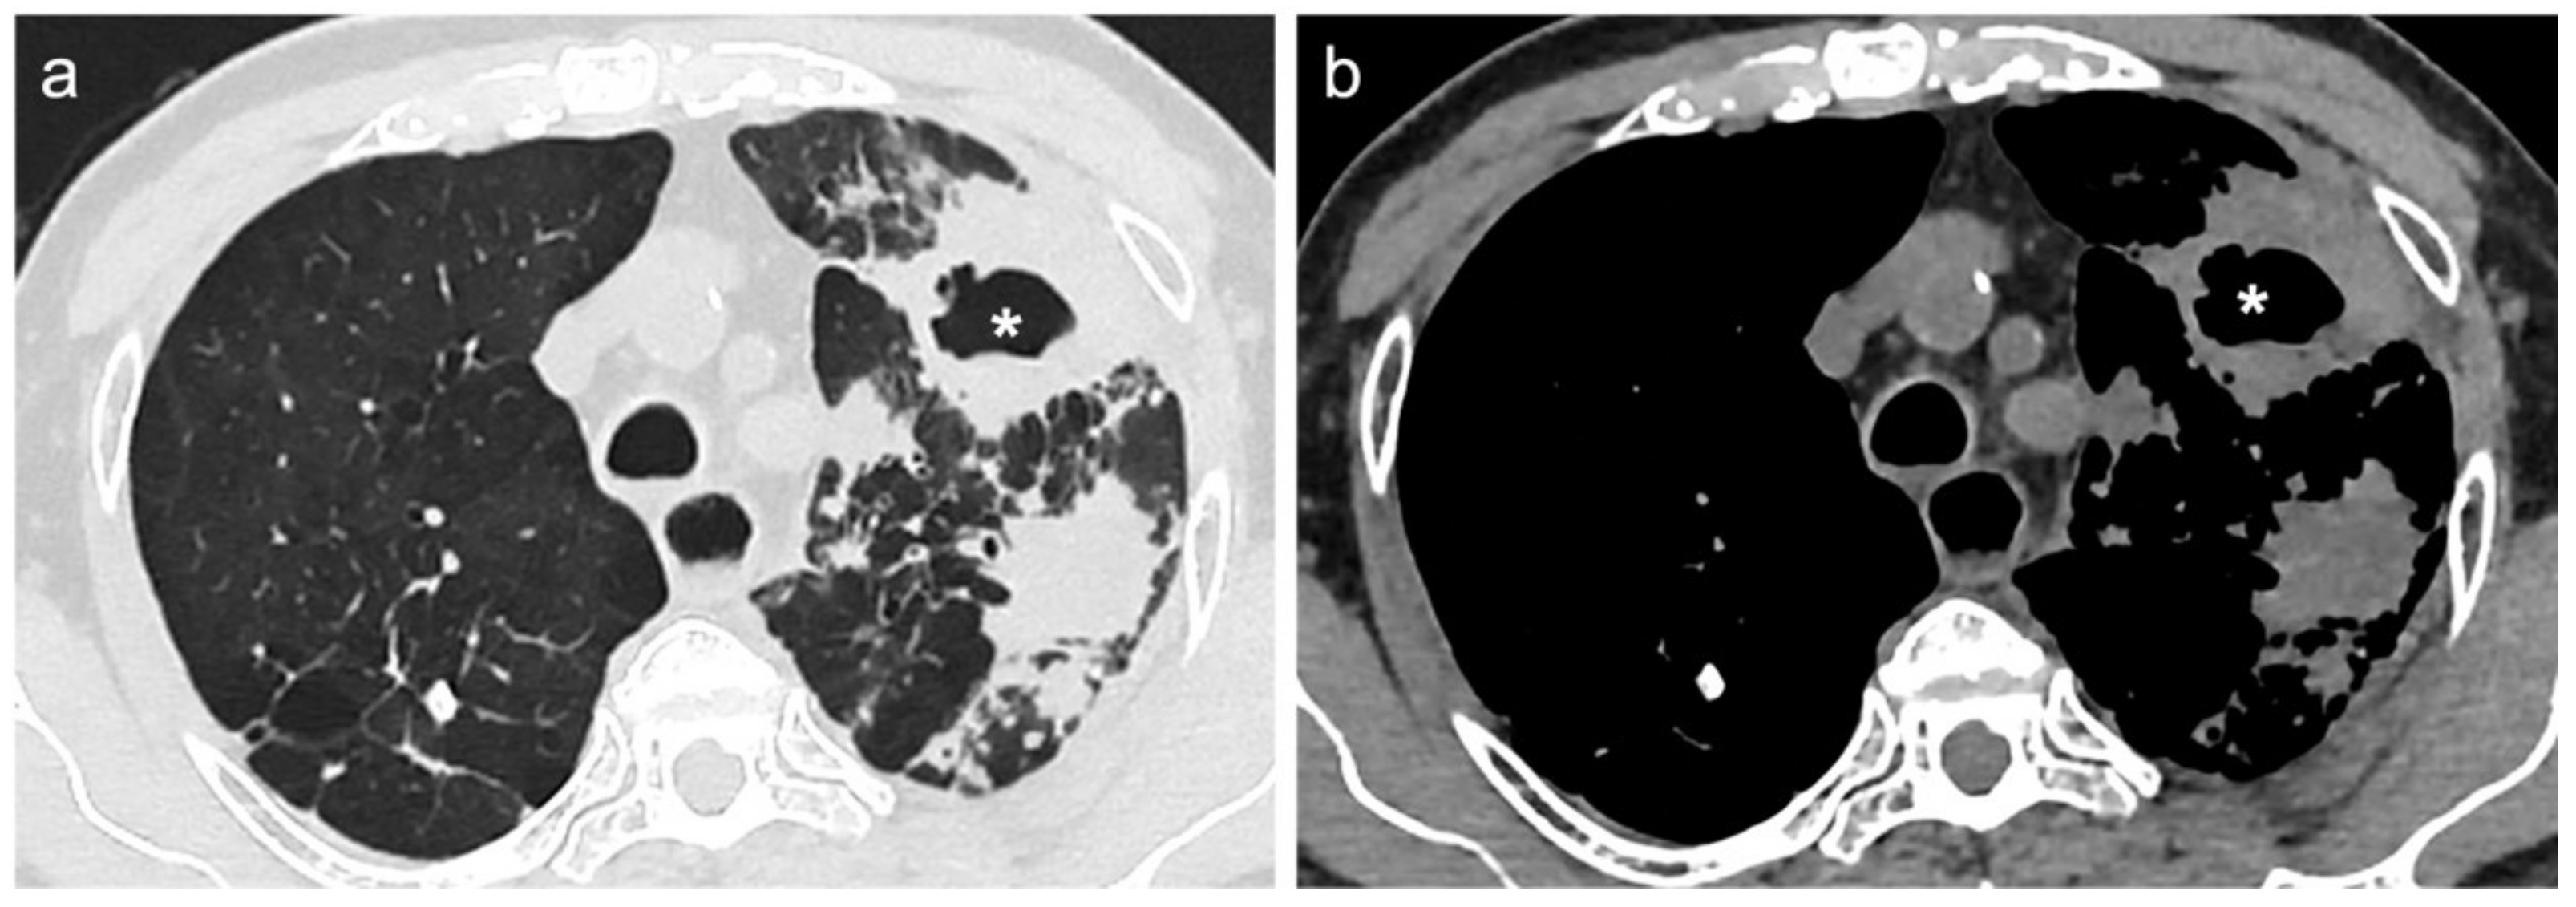

2.3. CT Scans Evaluation and Segmentation Analysis